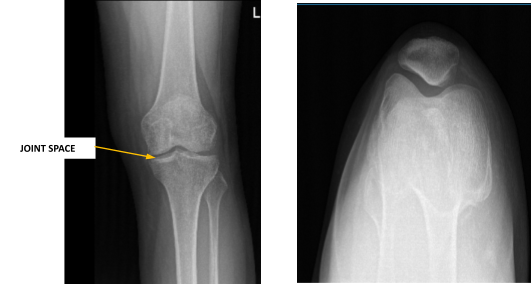

XR showed very mild left knee arthrosis, preferentially involving the medial compartment. Arthrosis occurs due to wear and tear of the cartilage at the joints. It usually happens because of aging or intense use of the joints during sports, exercise or other activities.

There is minimal joint space narrowing at the medial aspect of the medial femorotibial compartment. Very small marginal osteophytes are present. There is a very small left knee joint effusion.

Left knee X-ray complete with patella

MRI also performed and there is an oblique tear of the body and posterior horn of the medial meniscus and found medial and patellofemoral compartment articular cartilage defects. The patella is slightly subluxed laterally relative to the femur.